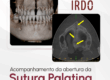

Porém, ao realizarmos a navegação de maneira adequada, associando os 3 planos e trabalhando escala de cinza, foi possível localizar e diferenciar um canal lateral nesta região (imagens 3,4 e 5), e que, não por coincidência, sua saída está localizada no epicentro da reabsorção óssea.

Canal lateral visível nos três planos

O diagnóstico só foi possível com navegação detalhada e uso correto da escala de cinza.

Saída do conduto lateral coincide com a área de reabsorção óssea